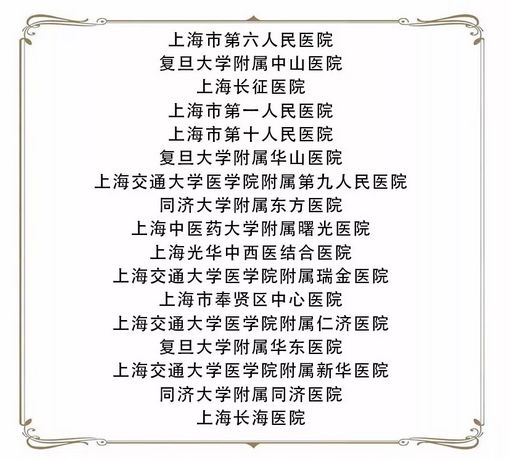

骨关节炎患者的福利 3月17日,上海关节外科顶尖专家将来奉义诊

医疗器械 关节置换手术 附2019年医疗专业大学排行榜